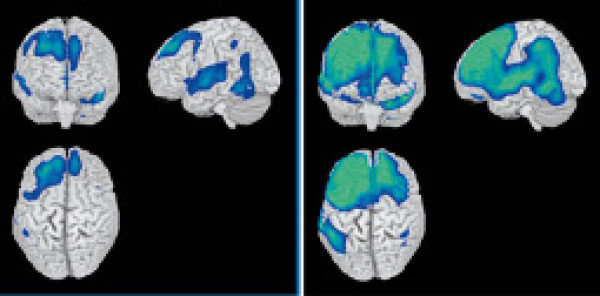

뇌졸중은 흔히 중풍이라고도 하며, 뇌에 혈액을 공급하는 혈관에 문제가 생겨 뇌 조직이 손상되는 질환입니다. 혈관이 막혀서 발생하는 경우를 뇌경색이라 하고, 혈관이 터져서 발생하면 뇌출혈이라고 부릅니다. 우리나라에서는 매년 수십만 명이 뇌졸중 초기 증상을 경험하는 것으로 보고될 만큼 흔한 질환입니다.

뇌졸중은 크게 두 가지로 나눌 수 있습니다. 하나는 혈관이 막혀서 생기는 뇌경색, 다른 하나는 혈관이 터져서 출혈이 일어나는 뇌출혈입니다. 또 혈관이 일시적으로 막혔다가 다시 뚫리며 증상이 잠깐 나타났다가 사라지는 일과성 허혈발작(일과성 허혈증)이 있는데, 이는 향후 뇌졸중 발생을 예고하는 중요한 신호로 간주됩니다.

뇌는 혈액 공급이 단 몇 분만 중단되어도 회복이 어려운 손상을 입을 수 있으므로, 뇌졸중 의심 시에는 신속한 병원 이송과 치료가 필수입니다. 치료 방법은 증상의 원인(뇌경색인지 뇌출혈인지)에 따라 달라집니다.